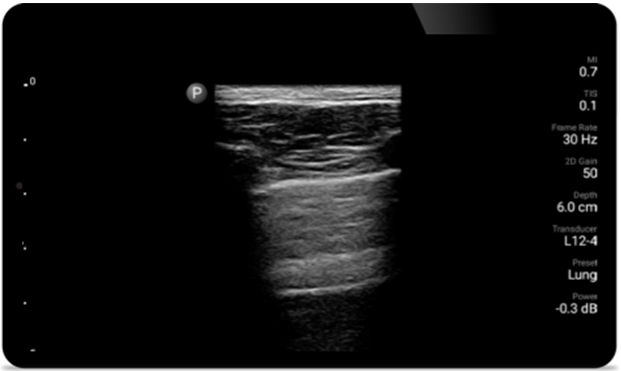

Breathe easier with Lumify

Lumify can help assess patients faster and improve accuracy when diagnosing common causes of dyspnea and other lung conditions.